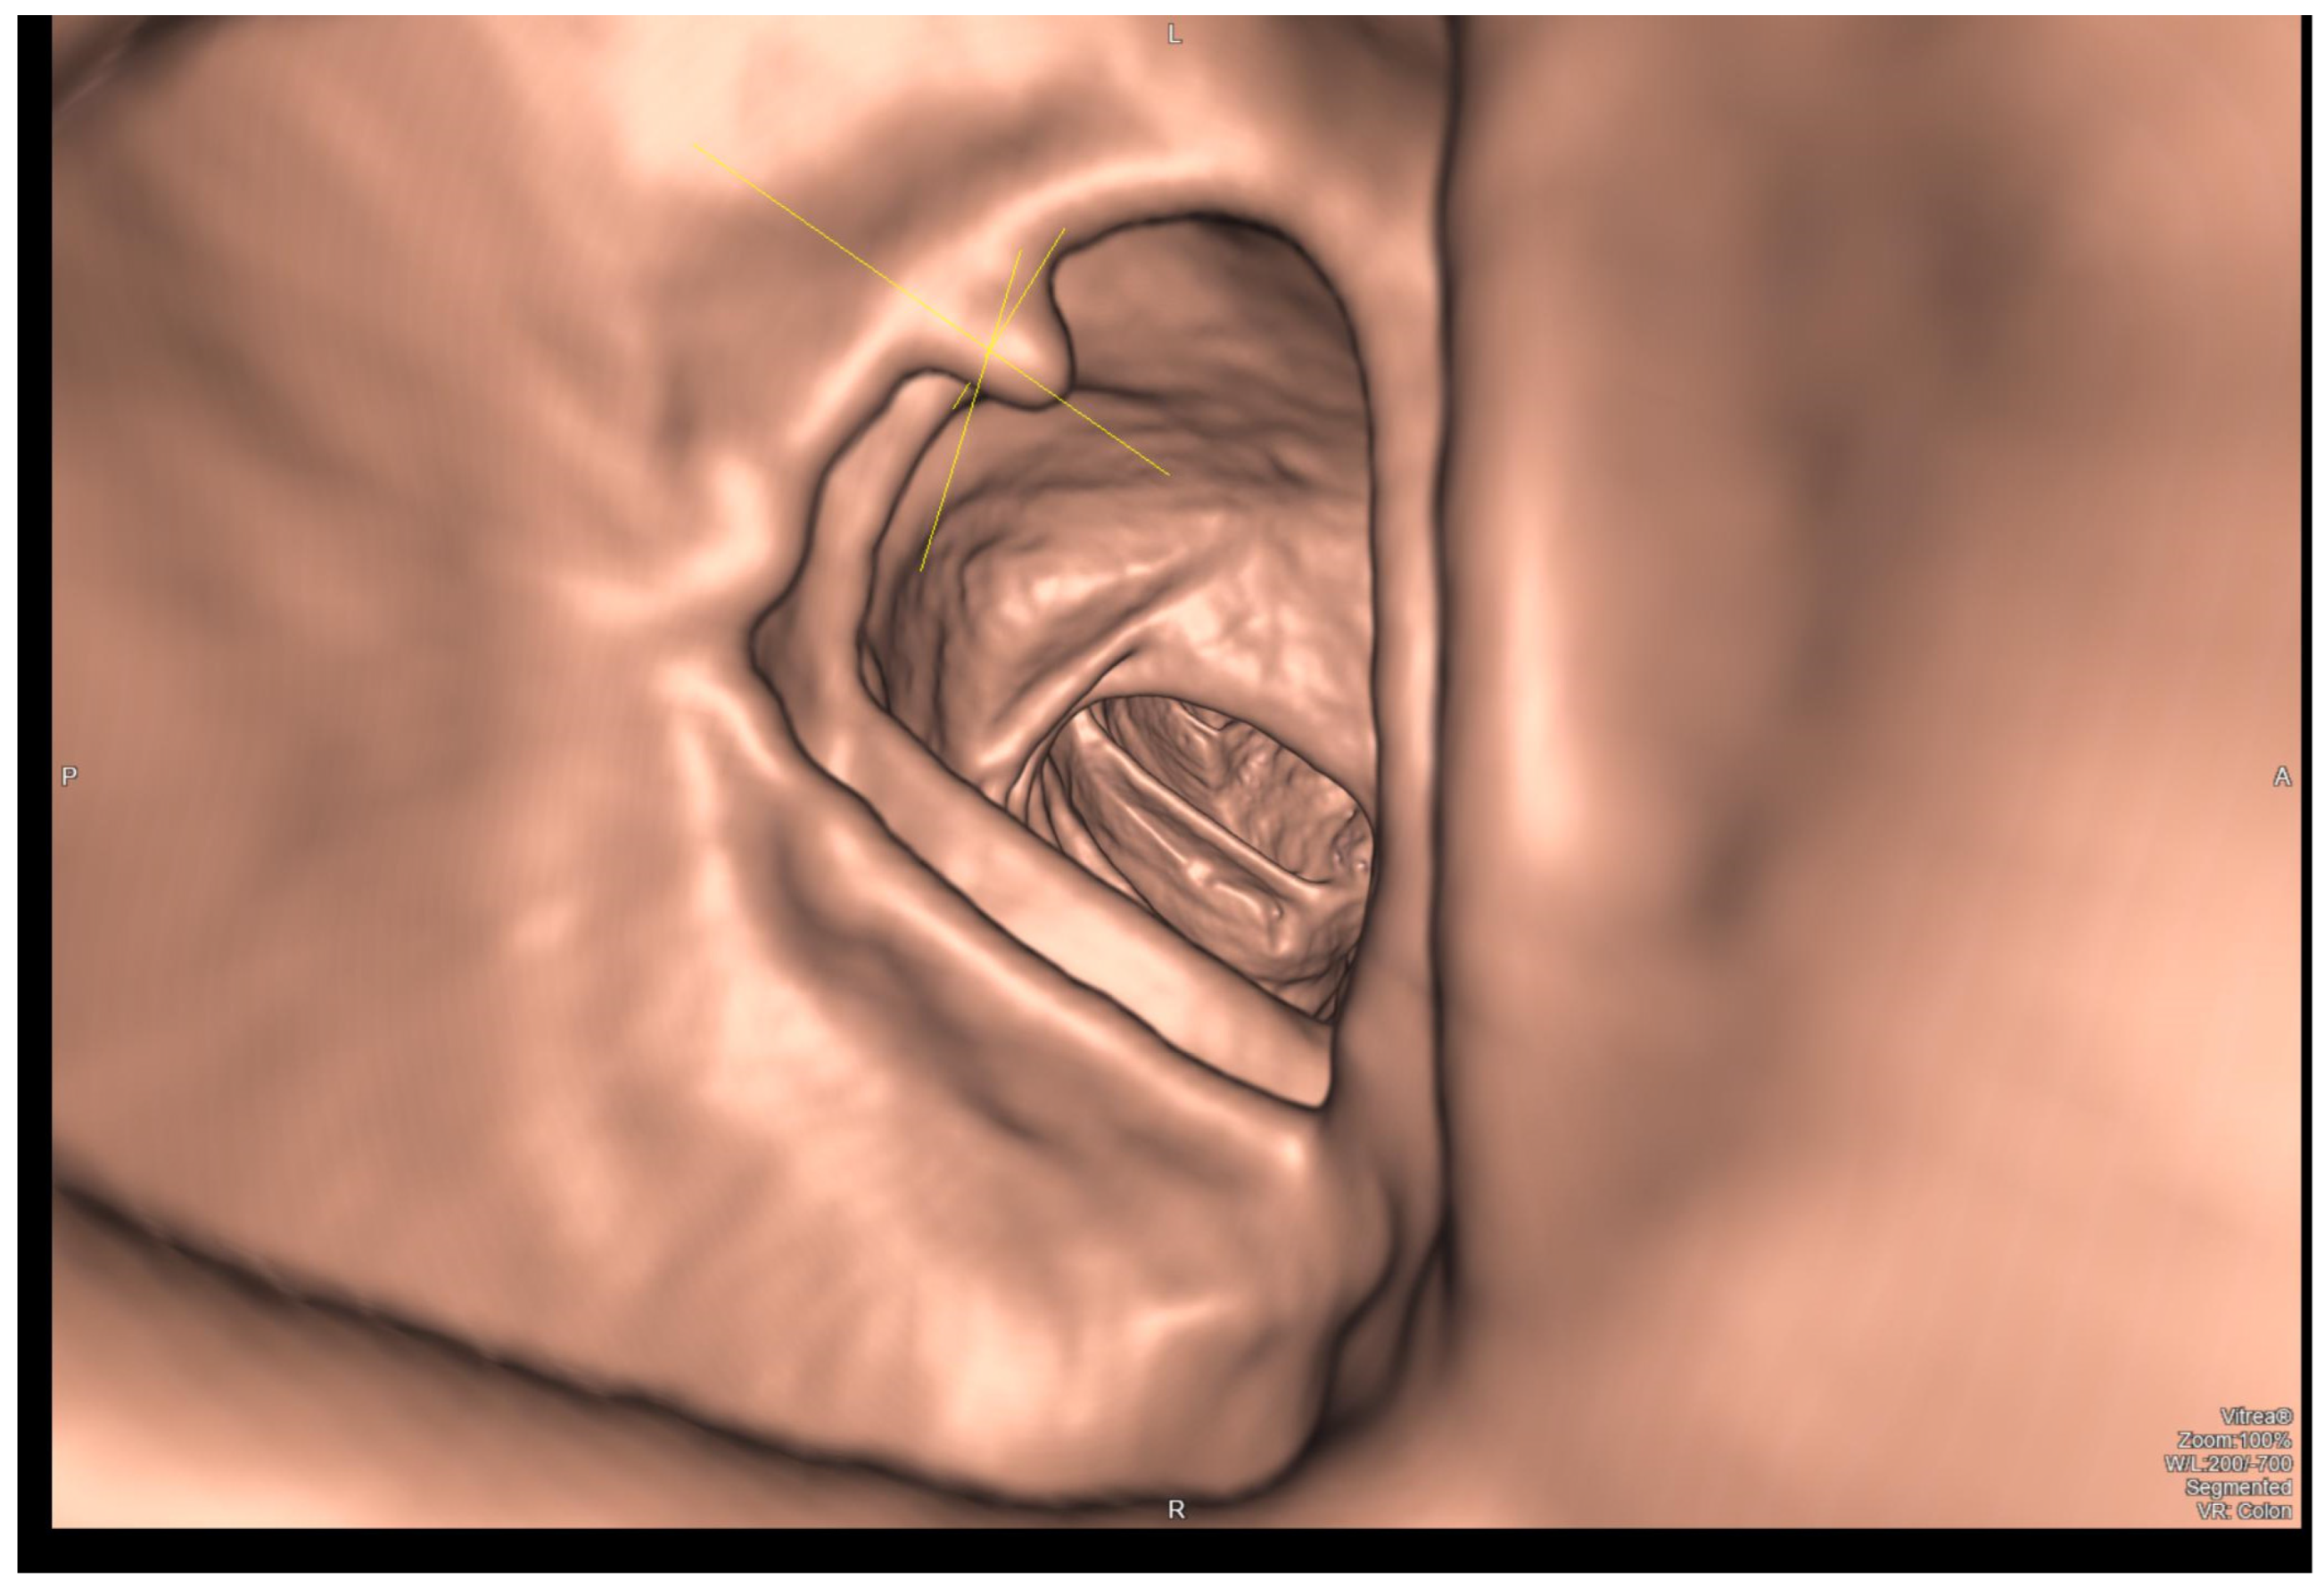

5. Virtual Colonoscopy (CTC)